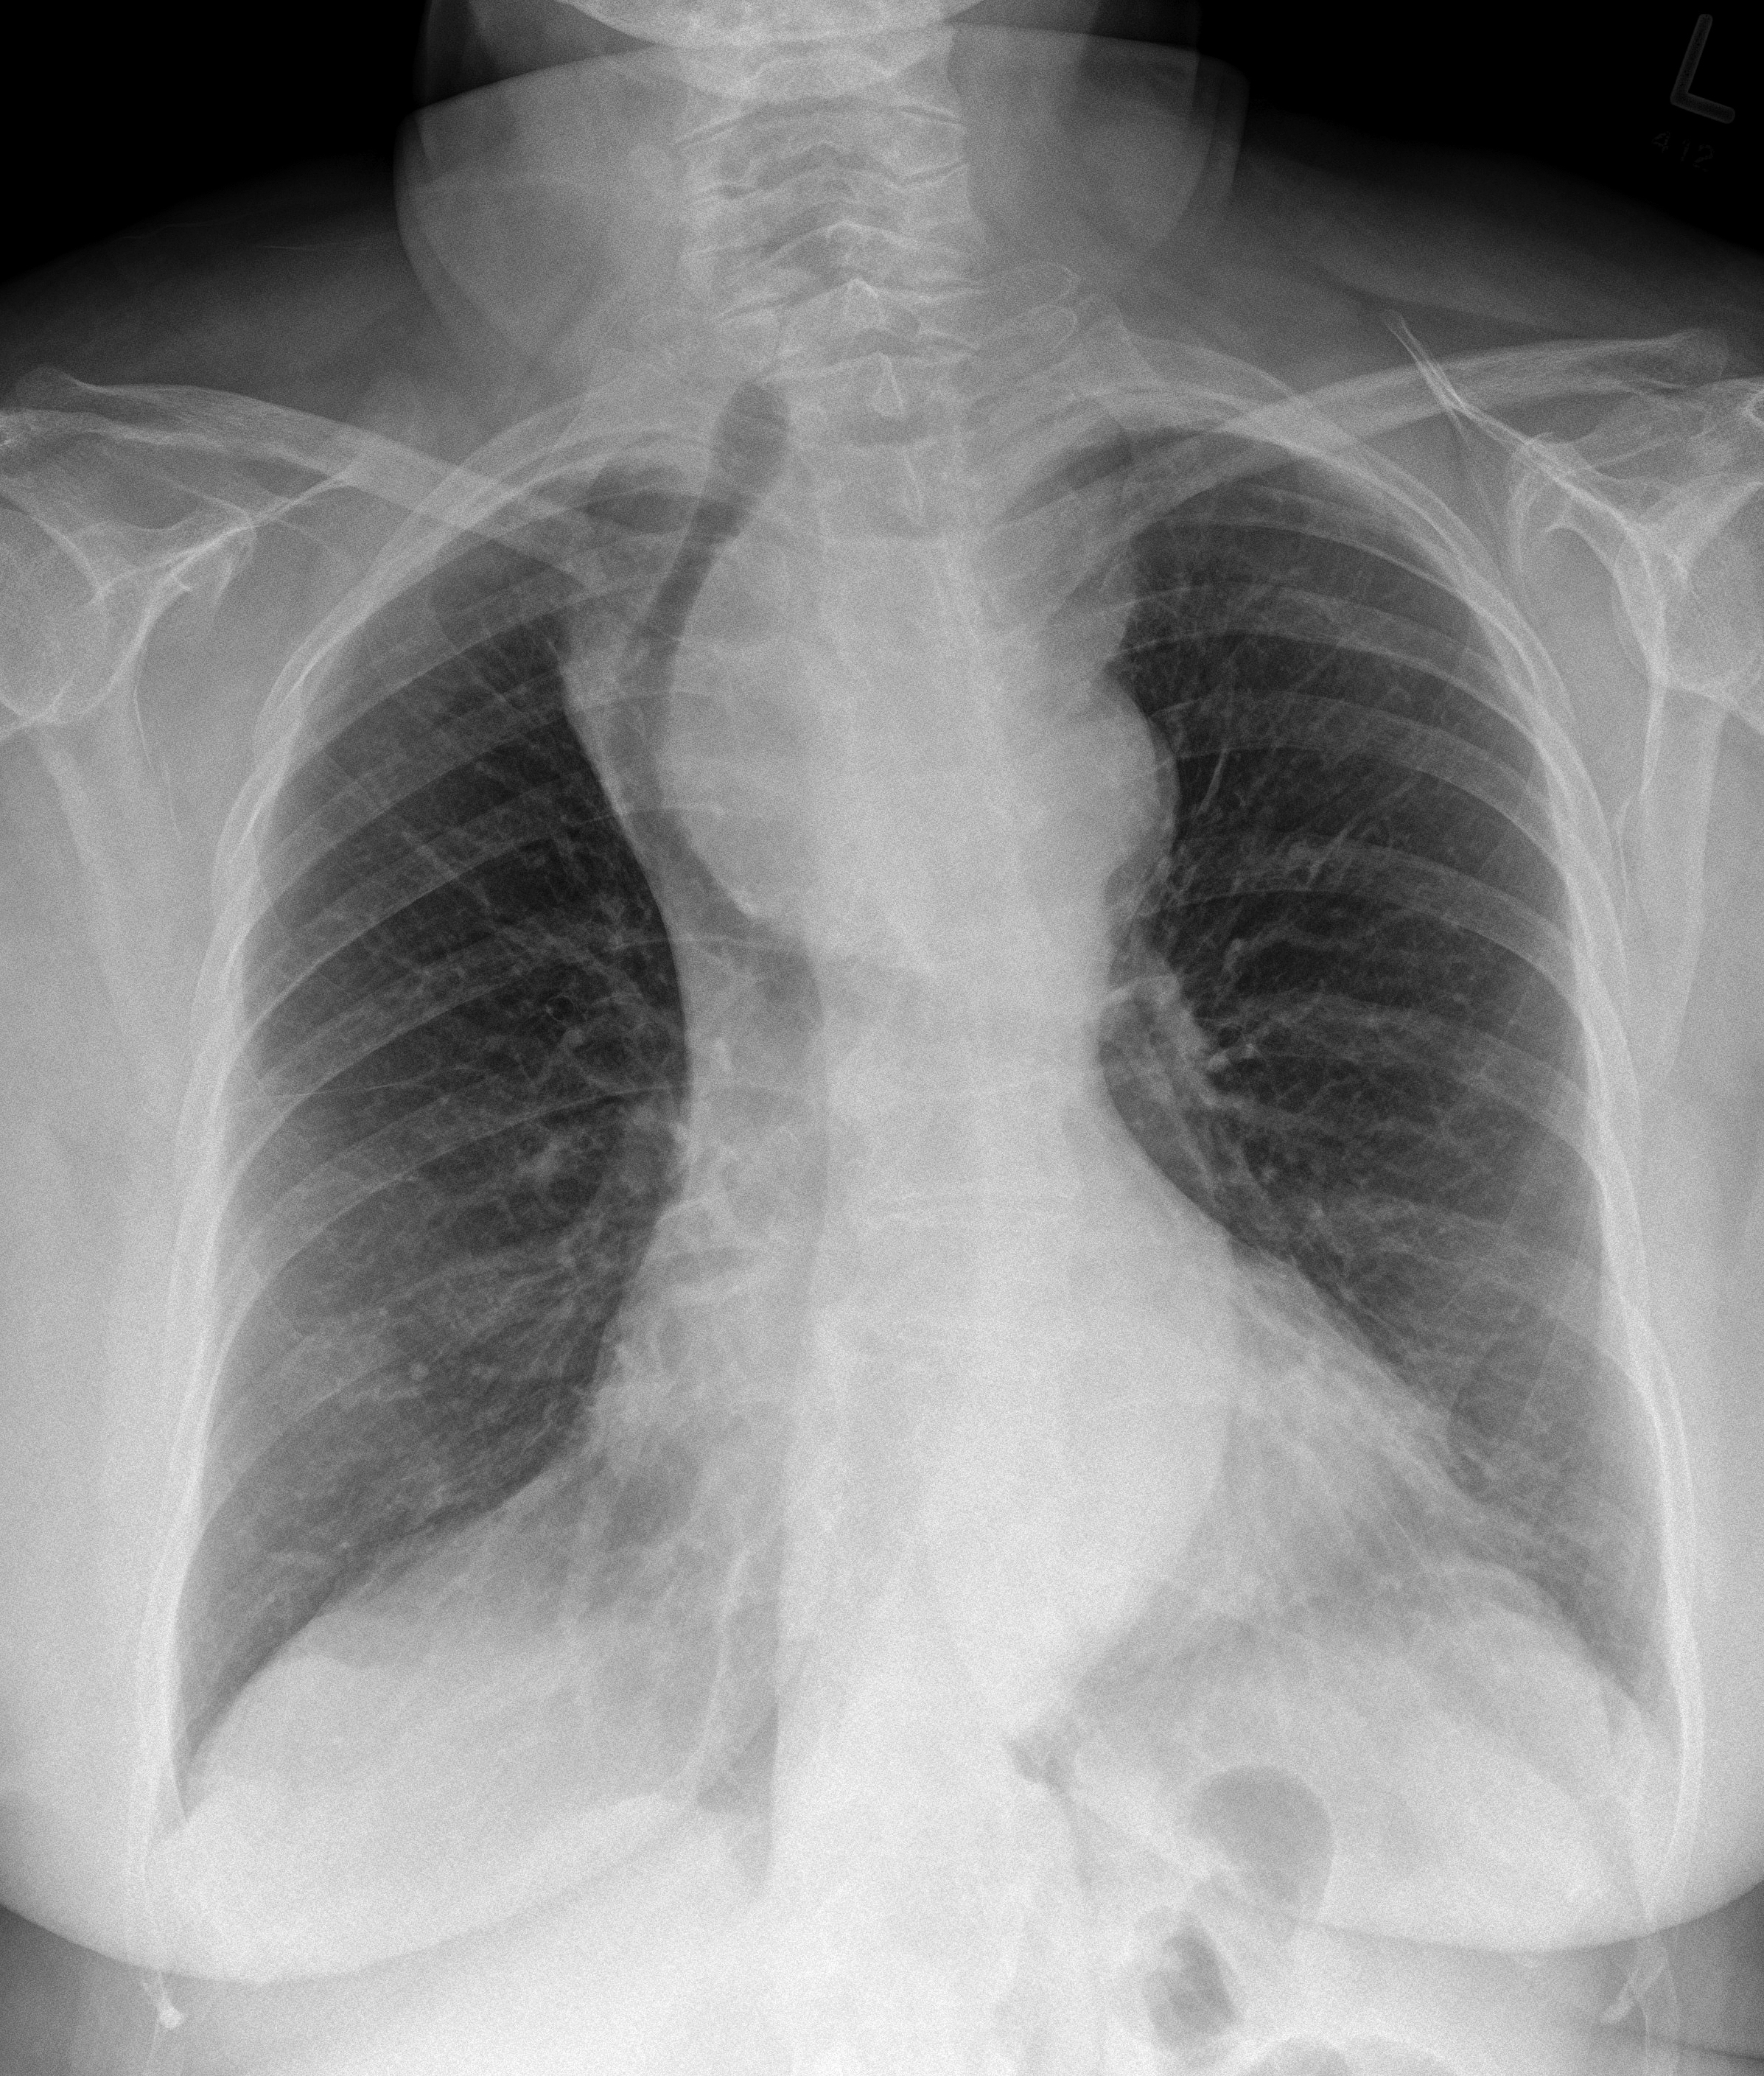

Retrosternal goitre PA